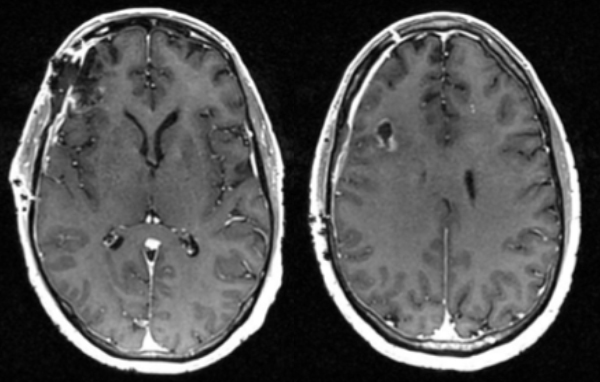

Pre-op

Post-op

Follow up imaging demonstrated a gross total resection for both intracranial metastases. The patient tolerated the surgery well and was discharged home on postoperative day four. At one-month follow-up, he was neurologically back to his baseline with a resolution of previous headaches and behavioral changes. He underwent postoperative stereotactic radiosurgery (Gamma Knife) to each surgical bed, followed by chemotherapy.

This is a 56-year-old man with a history of COPD and asthma who presented with a syncopal event and one week of retro-orbital headaches, blurry vision, and personality changes including apathy and disinhibition. He had a 40- pack-year smoking history but no prior malignancy. The exam revealed a pronator dri on the le upper extremity. MRI brain demonstrated 2 large right frontal heterogeneously enhancing masses with vasogenic edema causing midline shi and subfalcine herniation. The largest lesion was 3.9 x 4.0 cm on the inferior/sub frontal cortical surface, while the other was 3.0 x 2.7 cm in the superior subcortical frontal lobe. Further imaging showed a mediastinal mass suspicious for malignancy. He was started on Decadron for edema and Keppra for seizure prophylaxis.